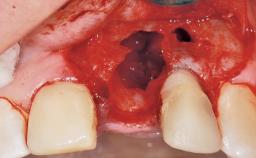

A 42-year-old female patient was referred to our clinic at the School of Dentistry of the University of São Paulo in November 2004, presenting a deficient restoration in the upper left central incisor. The clinical examination revealed no gingival retraction or any signs of gingival inflammation and, therefore, previous periodontal treatment was not considered. The patient presented a high lip line at full smile and a thin tissue biotype. This combination characterized a high-risk situation from an anatomic point of view, which required careful preoperative planning and cautious surgical execution.

Lip Line No exposure of papillae Exposure of papillae Full exposure of mucosa margin

Periodontal Phenotype Low-scalloped, thick Medium-scalloped, medium-thick High-scalloped, thin